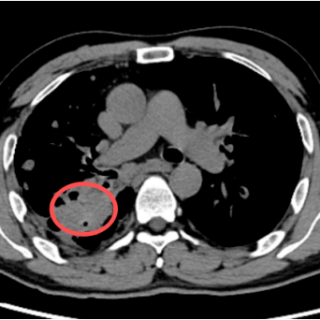

近日,在湘潭市第一人民医院放射科,上演了一场与死神的赛跑。一位年轻的肺结核患者突发咯血,命悬一线。幸运的是,医生凭借敏锐的洞察力,通过“支气管动脉CTA(即CT血管造影)”的检查,精准捕捉到了潜伏在其肺部深处的“隐形杀手”——Rasmussen动脉瘤。

Rasmussen动脉瘤,并非真正的肿瘤,而是一种“假性动脉瘤”,常发生于肺结核空洞患者,因结核病灶侵蚀肺空洞壁内的肺动脉分支血管壁,导致血管局部变薄、膨出,形成一个仅由纤维组织包裹的脆弱“气球”,极易破裂引发大出血,患者可能在短时间内因窒息或失血性休克而死亡。

为什么如此危险?Rasmussen动脉瘤伪装性强,在普通的胸部CT平扫中,这个动脉瘤可能仅仅表现为肺部的一个“结节”或“空洞内的软组织影”,极易被误诊为肺癌、炎症或普通的结核病灶;突发致命,它是导致肺结核患者大咯血的最主要原因,很多患者平时可能只有轻微的咳嗽或痰中带血,但一旦动脉瘤破裂,出血量往往巨大且迅猛;操作风险,若误诊为肿瘤并进行支气管镜活检或经皮肺穿刺,那无异于“引爆”炸弹,会导致瞬间的大出血,后果不堪设想。

在湘潭市第一人民医院的这例抢救中,支气管动脉CTA技术发挥了至关重要的作用。普通CT平扫,只能看到“山的轮廓”,可能只觉得那里有个包块。而支气管动脉CTA相当于给血管注入了“显影剂”,能清晰地看到“山里的水流”。它能明确显示病灶是否由血管组成,明确动脉瘤的位置、大小以及供血血管,为治疗提供精确“导航”,避免盲目操作带来的风险。